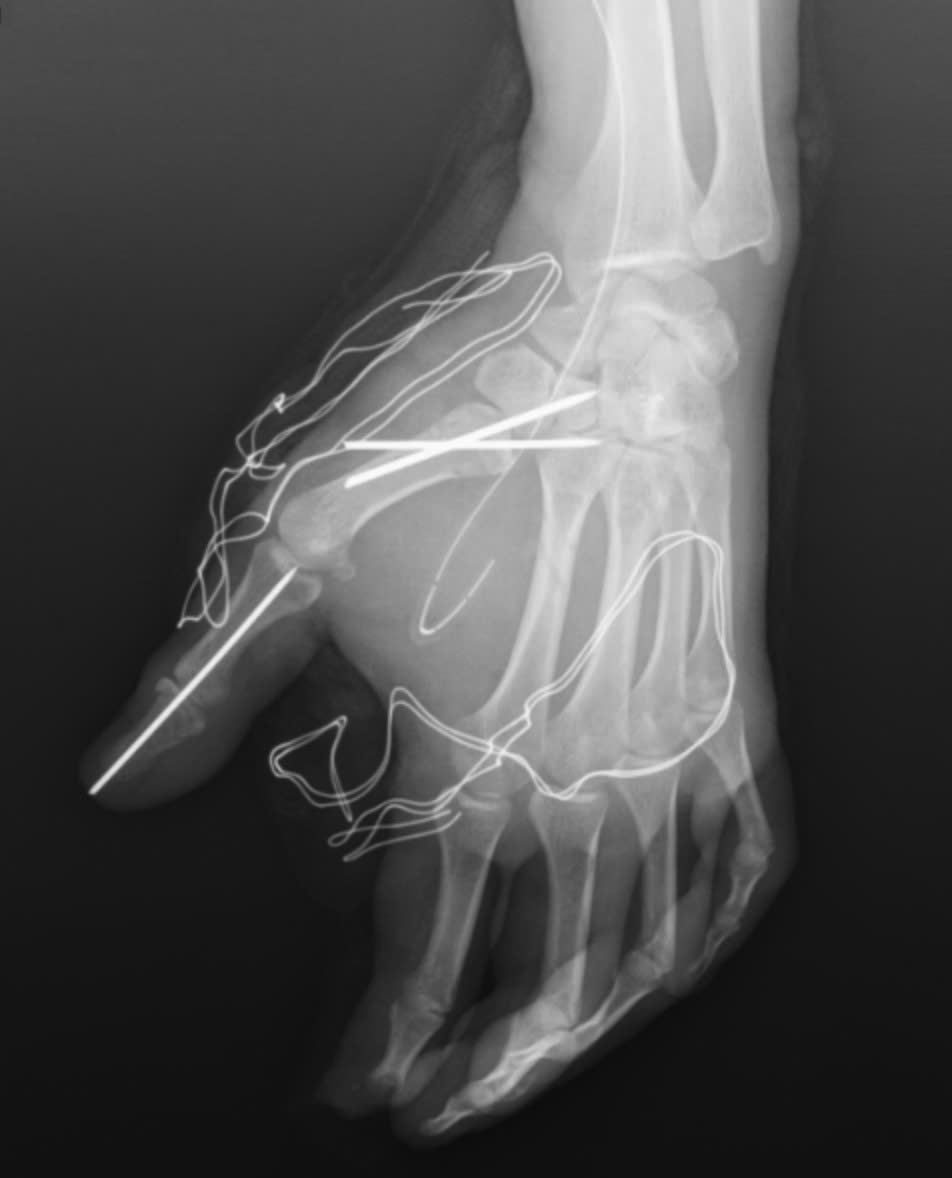

Trong quá trình phẫu thuật, các bác sĩ khoa Phẫu thuật Chấn thương Chỉnh hình và Y học thể thao đã tiến hành cắt lọc tổ chức dập nát, lấy bỏ dị vật trên bàn tay của người bệnh. Đồng thời, vết thương được làm sạch, các cấu trúc gân, thần kinh và mạch máu còn lại được bảo tồn tối đa. Cuối cùng, các bác sĩ cố định xương gãy và khớp bị trật cho người bệnh.

Bàn tay nạn nhân bị dập nát sau tai nạn pháo nổ.